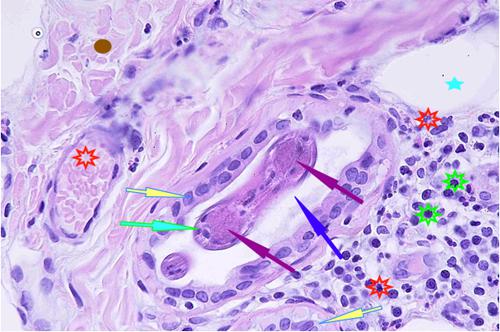

Photo 4 (Hémalun-Eosine X200) peau velue : Vue rapprochée de la Photo 3 montrant

la zone de fissuration de la gaine épithéliale externe d’un infundibula folliculaire avec lyse des

attaches desmosomiales intercellulaires et afflux de granulocytes éosinophiles donnant

naissance à des micro-pustules pariétales multiloculaires.

Légendes de la Photo 4 :

- Double flèche verte : grand axe de l’infundibulum folliculaire

- Double flèche rose : épiderme

- Flèches jaunes : fissuration de la gaine épithéliale externe avec lyse des attaches desmosomiales intercellulaires et afflux de granulocytes éosinophiles

- Ronds marrons : parakératose

- Étoiles rouges : micro-pustules pariétales multiloculaires (folliculite murale) et luminales obstruant l’abouchement folliculaire

- Étoiles turquoises : à gauche infiltrat inflammatoire dermique (au milieu en bas, erreur)

- Étoile vertes : orthokératose